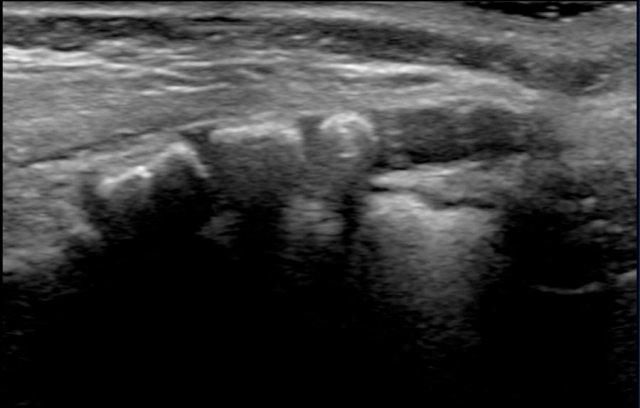

Tủy sống được hiển thị là một cấu trúc giảm âm rõ rệt với vùng tăng âm ở trung tâm.

Vùng tăng âm trung tâm này được cho là đại diện cho ranh giới giữa mép trước và rãnh giữa trước, chứ không phải ống trung tâm.

Hình ảnh cắt ngang tủy sống với vùng tăng âm trung tâm.

Hình ảnh cắt ngang vùng đuôi ngựa.

Luôn luôn thu nhận hình ảnh trên mặt phẳng cắt ngang.

Sự di động của các rễ thần kinh được quan sát rõ hơn trên mặt phẳng ngang so với mặt phẳng đứng dọc, đồng thời dễ dàng hơn trong việc đánh giá bệnh lý trong ống sống như filum terminale dày.

Ghi hình ở tư thế nằm nghiêng phải.

Các rễ thần kinh tập trung ở phía phụ thuộc trọng lực nhưng di động tự do.

Khi các rễ thần kinh không di động tự do, đây có thể là dấu hiệu của OSD.